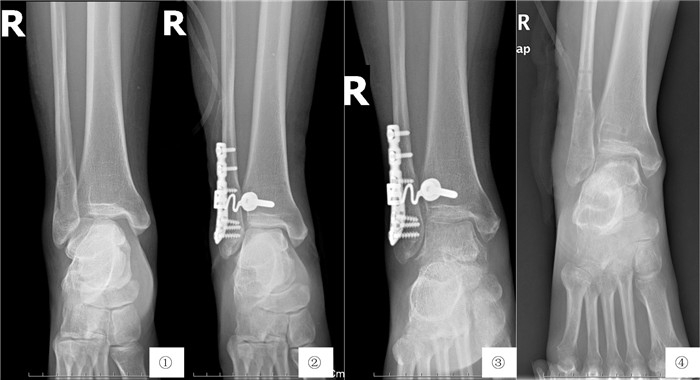

2 结果本组2例患者在术后3月失去随访,术中、术后均未出现并发症,亦未获得踝关节功能评分结果,其余10例均获得24~36个月临床随访,平均32.4个月。随访期间定期行X片检查,未出现下胫腓联合分离或内固定物脱落。所有10例患者于术后8~12个月行内固定物取出,(10.3±0.8)个月。末次随访根据Olerud and Molander踝关节功能评分进行评定,平均93分,其中优(>90分)6例,良(>80分)4例,无1例评分<80分(表 1)。4例患者评分低于90分仅因轻度踝关节肿胀和僵硬所引起,所有10例患者均回到术前工作岗位继续工作,均未出现伤口感染、内固定物松动及排异反应等并发症的发生。典型病例见图 2。

| 图 2 ①术前右侧踝关节正位X线片;②术后2 d右侧踝关节正位X线片;③术后3月右侧踝关节正位X线片;④术后1年内固定取出后右侧踝关节正位X线片 |